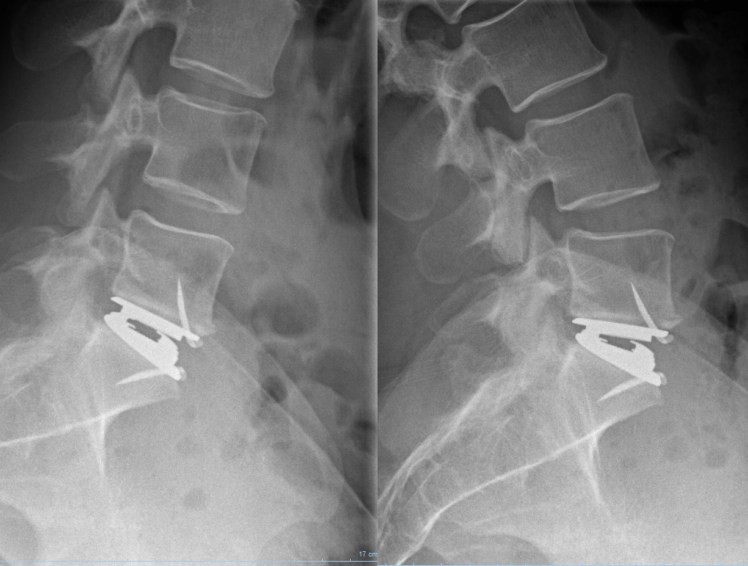

Control the mobility of a Maverick prosthesis after 9 years :

– perfectly functional prosthesis

– the patient has taken a social and working life strictly normal (military)

– He remains painless